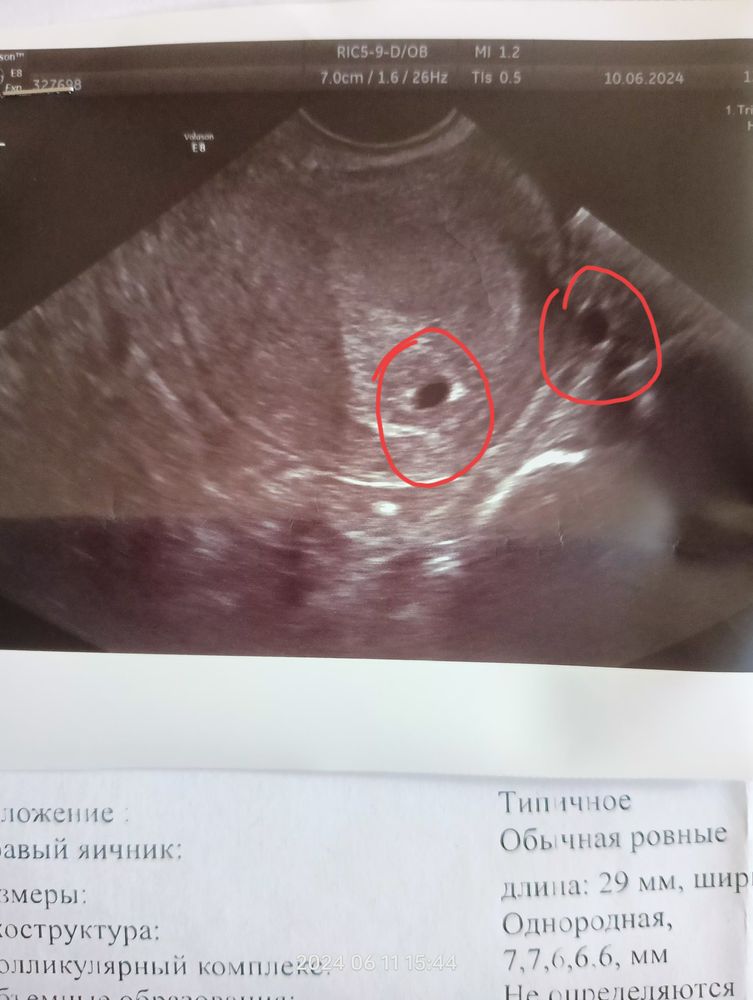

Врач пишет что беременность одноплодная, но заметила на снимке ещё одно пятнышко, скажите могут ли так располагаться двойня?

Второе пятнышко за пределами матки. Либо срез сосуда, либо кишки.